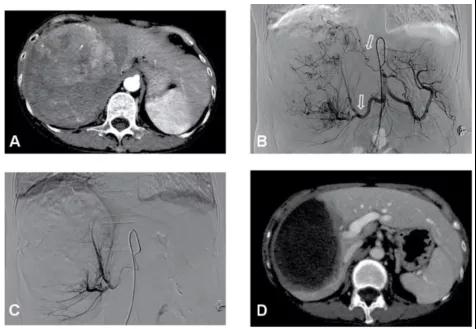

图3、该例大于15cm的巨大肝癌,经过2次DEB-TACE联合FOLFOX HAIC治疗,肿瘤明显缩小和肿瘤完全坏死。